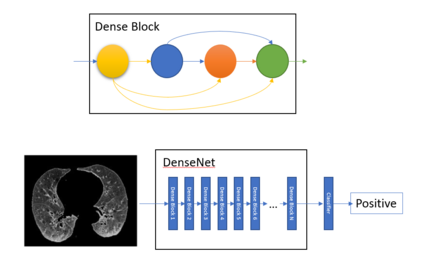

COVID-19 infection caused by SARS-CoV-2 pathogen is a catastrophic pandemic outbreak all over the world with exponential increasing of confirmed cases and, unfortunately, deaths. In this work we propose an AI-powered pipeline, based on the deep-learning paradigm, for automated COVID-19 detection and lesion categorization from CT scans. We first propose a new segmentation module aimed at identifying automatically lung parenchyma and lobes. Next, we combined such segmentation network with classification networks for COVID-19 identification and lesion categorization. We compare the obtained classification results with those obtained by three expert radiologists on a dataset consisting of 162 CT scans. Results showed a sensitivity of 90\% and a specificity of 93.5% for COVID-19 detection, outperforming those yielded by the expert radiologists, and an average lesion categorization accuracy of over 84%. Results also show that a significant role is played by prior lung and lobe segmentation that allowed us to enhance performance by over 20 percent points. The interpretation of the trained AI models, moreover, reveals that the most significant areas for supporting the decision on COVID-19 identification are consistent with the lesions clinically associated to the virus, i.e., crazy paving, consolidation and ground glass. This means that the artificial models are able to discriminate a positive patient from a negative one (both controls and patients with interstitial pneumonia tested negative to COVID) by evaluating the presence of those lesions into CT scans. Finally, the AI models are integrated into a user-friendly GUI to support AI explainability for radiologists, which is publicly available at http://perceivelab.com/covid-ai.